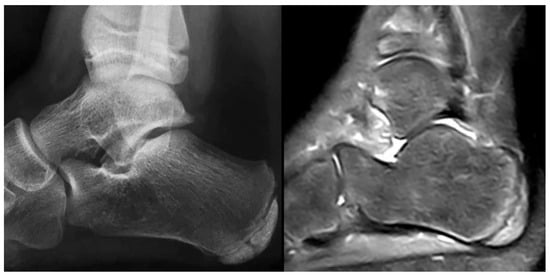

Figure 3.

Eleven-year-old male patient. Radiograph (left) demonstrating typical fragmentation and bipartite appearance of the calcaneal apophysis. MRI (right) showing detailed fragmentation with associated bone marrow edema.

Figure 4.

Ten-year-old male patient. Radiograph (left) revealing marked fragmentation, thinning, and bipartition of the calcaneal apophysis. MRI (right) demonstrating extensive associated bone marrow edema.